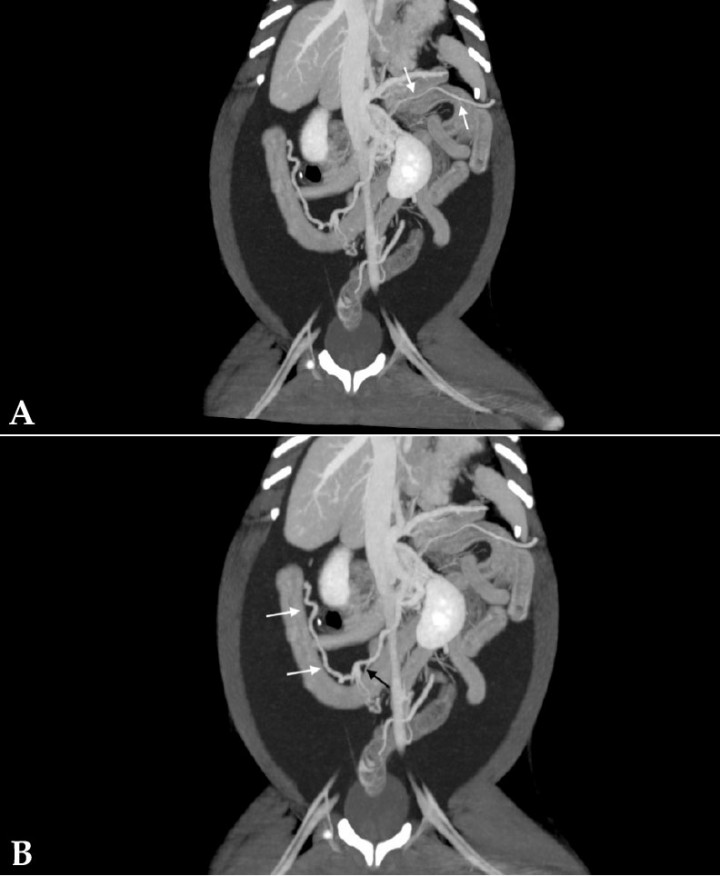

- Desde la vena esplénica, un vaso anómalo y aberrante, caudal y medial al riñón izquierdo, con la confluencia de otros vasos de menor calibre, era consistente con una comunicación esplenorrenal (Fig. 9A). También se observó la presencia de un vaso anómalo y tortuoso que partía de la vena pancreatoduodenal con dirección hacia caudal para terminar en la vena mesentérica caudal (Fig. 9B).

<p>Imágenes de tomografía computarizada dorsales tras la administración de contraste intravenoso, ventana de tejido blando y con proyección de máxima intensidad (MIP) con sumatorio de cortes. (<strong>A</strong>) Se observa un vaso anómalo a partir de la vena esplénica que se dirige hacia caudal y medial del riñón izquierdo (flechas). (<strong>B</strong>) Se aprecia un vaso anómalo a partir de la vena pancreaticoduodenal (flechas blancas) que desemboca en la vena mesentérica caudal (flecha negra).</p>

Figura 9

Imágenes de tomografía computarizada dorsales tras la administración de contraste intravenoso, ventana de tejido blando y con proyección de máxima intensidad (MIP) con sumatorio de cortes. (A) Se observa un vaso anómalo a partir de la vena esplénica que se dirige hacia caudal y medial del riñón izquierdo (flechas). (B) Se aprecia un vaso anómalo a partir de la vena pancreaticoduodenal (flechas blancas) que desemboca en la vena mesentérica caudal (flecha negra).